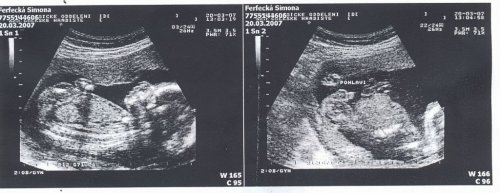

SRPŇÁTKA 2007 - fotky UTZ

album věnované mimískům, které se narodí v srpnu 2007 a jejich maminkám ze "Společného termínu SRPEN"